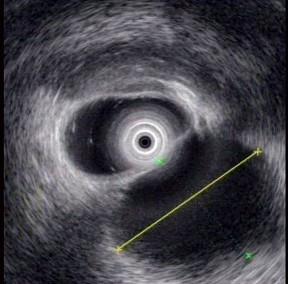

问题 男性,25岁。因急性胰腺炎住院1周,出院3周后仍有持续性上腹痛和背痛。查体无发热,在中上腹可触及一界限不清的包块,无压痛。血白细胞计数及分类正常,血清淀粉酶800苏氏单位。超声内镜如图中胰腺病变可能的诊断是 ( )

选项 A.胰腺假性囊肿 B.胰腺真性囊肿 C.慢性胰腺炎 D.胰腺囊腺癌 E.胰腺癌

答案 A